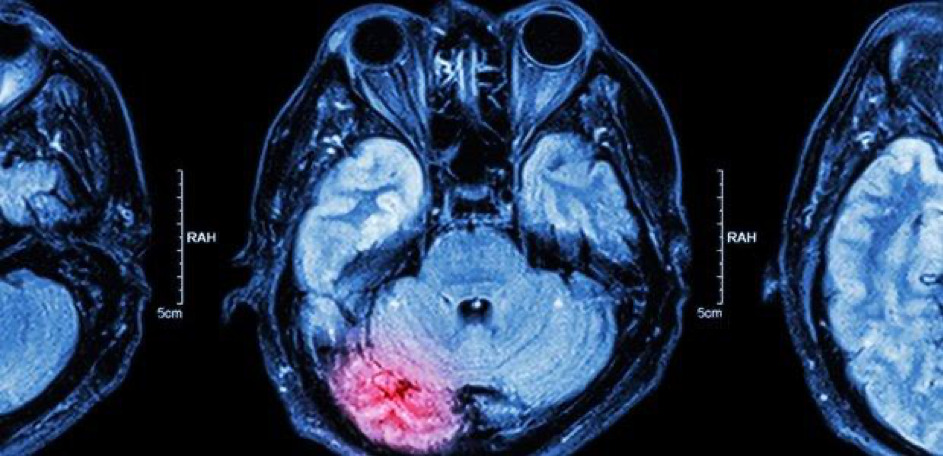

6. Phục hồi sau đột quỵ xuất huyết não

Đột quỵ xuất huyết xảy ra do chảy máu đột ngột xung quanh não. Dạng đột quỵ này chiếm khoảng 15% tổng số ca đột quỵ. Thời gian hồi phục phụ thuộc vào việc chảy máu trong não hay trong thân não.

Đối với đột quỵ trong não, nói chung có nguy cơ thấp hơn và thời gian phục hồi ngắn hơn; hầu hết lợi nhuận được thực hiện trong 3 tháng đầu tiên. Nếu đột quỵ ảnh hưởng đến thân não, quá trình hồi phục có thể mất một năm hoặc hơn.